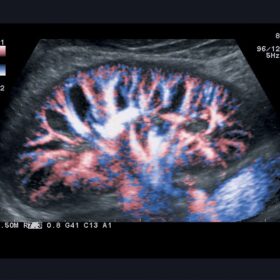

Ultrasound Aloka Prosound Alpha 10 – Image Gallery and Videos

Enhanced image quality ensures more accurate and efficient diagnosis while increasing patient satisfaction. The ideal choice for a large office or hospital imaging department. The Alpha 10 combines a 12 Bit A/D digital beam converter. High powered image processing channels and the exclusive probe technology to take examinations to the next level.

Sophisticated beam control provides high resolution and penetration while minimizing image degradation. While user-oriented operability and ergonomics create the ideal environment for fast and accurate imaging and diagnoses. The Alpha 10’s Extended Pure Harmonic Detection is a digital pure beam-imaging platform. That incorporates state-of-the-art acoustic technology that dramatically improves the clarity of the ultrasound beam formation and signal processing.

Striving to eliminate undesirable sound components from the transmitted ultrasound beam itself and with the ever-evolving ProSound technologies ALOKA has created the ProSound A10 platform. With its Ultimate Compounding Technologies, stress-free operation and combination of versatility and performance, the Aloka Prosound Alpha 10 provides the capability for a wide range of sophisticated diagnoses.

- Compound Array Probes enhance focus precision in the elevation direction and enable beams to be focused homogeneously from superficial to deep areas of interest.

RT-3D (4D)

Aloka ASU-1010 3D/4D Convex

Aloka ASU-1012 3D/4D Vaginal